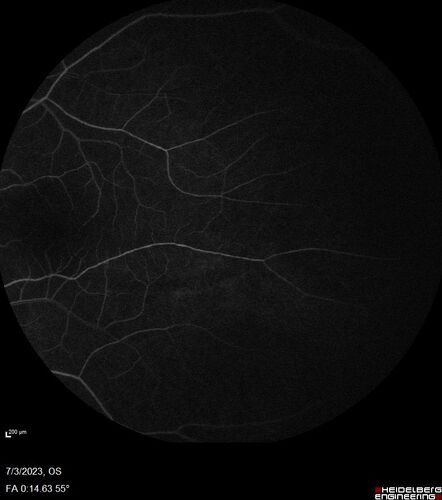

Choroidal macrovessel

70 year old female with vision loss in the left eye 4 months after cataract surgery.

VA 20/32 OD, 20/80 OS

Images show CME but also a choroidal macrovessel in the left eye.